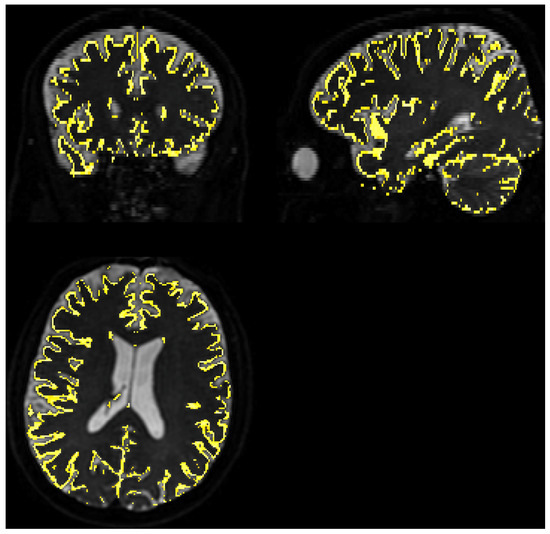

3.3.1. Quality of Matching Subject IVIM DWI Data to T2 MNI Template

3.3.2. Calculation of IVIM Parameters